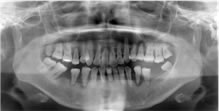

③ レントゲン検査

骨が溶けた所や血が出やすい所、グラグラしている所もチェックしています。